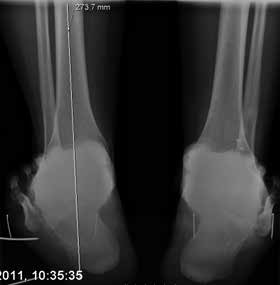

Als nächstes werden Röntgenaufnahmen des Fußes in 2 Ebenen, des oberen Sprunggelenkes in 2 Ebenen und eine Saltzman-Aufnahme zur Beurteilung der Rückfußachse angefertigt. Wichtig dabei ist, dass die Untersuchungen unter Belastung erfolgen, um die Achsverhältnisse des Fußes genau beurteilen zu können und um Varus- oder Valgusarthrosen des Sprunggelenkes frühzeitig zu erkennen. Gehaltene Aufnahmen werden auch bei der chronischen Instabilität nicht empfohlen 17.